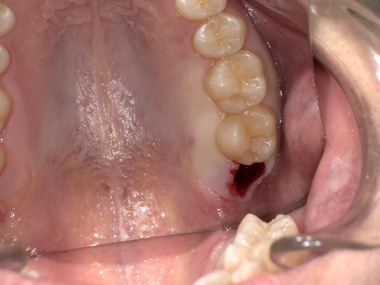

After(抜歯後)

上の親知らずを安全に抜歯

下の歯茎への噛み込みが解消

痛みと腫れが改善傾向へ

局所麻酔ののち、2〜3分で抜歯完了

上の親知らずは比較的抜きやすく、この症例でもスムーズな抜歯が可能でした。